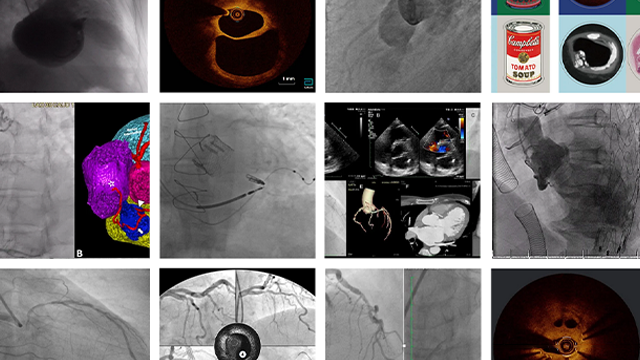

Examine some of the most striking images submitted to EuroPCR 2024. Shared by the community, they are up for discussion online!